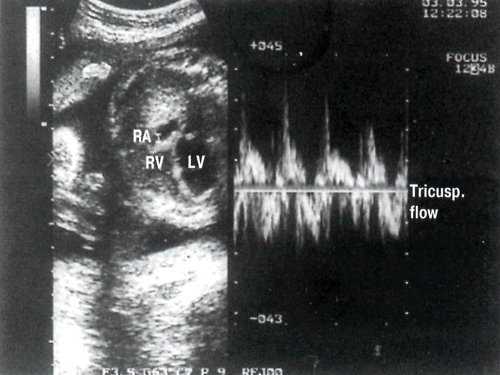

В отличие от митрального клапана, кровоток через трикуспидальный клапан увеличен. Выявляется также трикуспидальная регургитация (рис. 4).

Рис. 4. В-сканирование четырехкамерного сечения сердца плода и оценка кровотока через трикуспидальный клапан. Контрольный объем в полости правого предсердия. LV - левый желудочек. RV - правый желудочек.